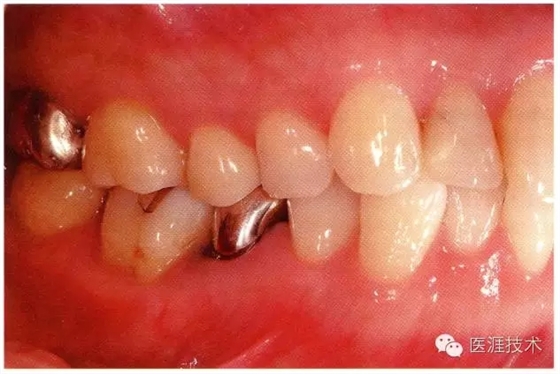

56歲牙周炎男性的臨床照片

640.webp (15).jpg

正在服用高血壓藥中的56歲男性。菌斑控制得不好。通過牙周探診,全頜有4~6mm的牙周袋,在X光片中可以看到全頜中度牙槽骨吸收,磨牙處一個(gè)地方是重度牙槽骨吸收。通過比較牙周病進(jìn)展?fàn)顟B(tài),邊緣部有大范圍浮腫(發(fā)紅、腫脹),和纖維性肥厚。這也可能是服用中的降壓藥的副作用導(dǎo)致的。因?yàn)檠例l、牙槽骨比較厚,牙齦呈架子狀。